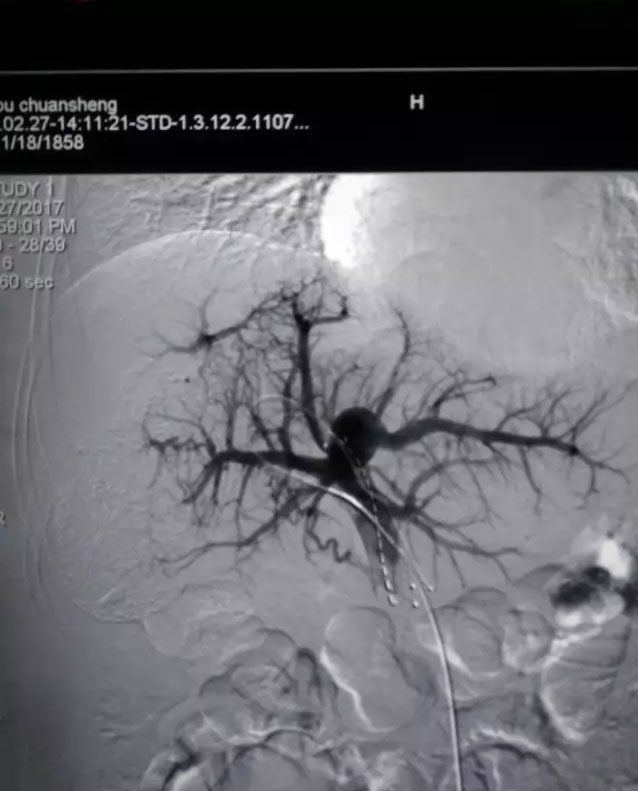

“经颈静脉肝内门体静脉分流”(TIPS)新技术是治疗晚期肝硬化的一剂良方。近三年来,放射介入中心已经成功为四十余位患有肝硬化合并腹水及反复消化道出血的患者取得十分满意的效果。这项新技术的推广应用取代了以往的“肝移植”传统的治疗方法。

家住凤台县焦岗乡的詹某某,在外打工近30年,因长期患有乙肝,未予以重视,病情加重形成肝硬化致腹水、反复吐血、黑便。多地求医无效,已花光家中积蓄,家中房产已变卖,辗转上海就诊后建议行TIPS,因医疗费用高昂无力支付放弃治疗。回淮南后听人介绍来到总院放射介入中心就诊,经过医务人员分析研究后,决定行TIPS手术治疗。术中从患者右颈部切开3毫米的切口,用一根细长的导管穿过心脏,进入肝静脉中,将肝静脉与门静脉穿刺贯通,植入支架,建立一条门静脉至肝静脉的管路通道。此通道将分流门静脉三分之一的血流,从而大大降低门静脉压力,有效缓解门静脉高压,进而缓解顽固性腹水及消化道出血。手术后,詹某某第2天即可下床活动,全身上下仅颈部一细小针眼的痕迹,呕血、黑便消失,腹围缩小。再次复查常规,白细胞、血小板、血红蛋白基本恢复正常指标。